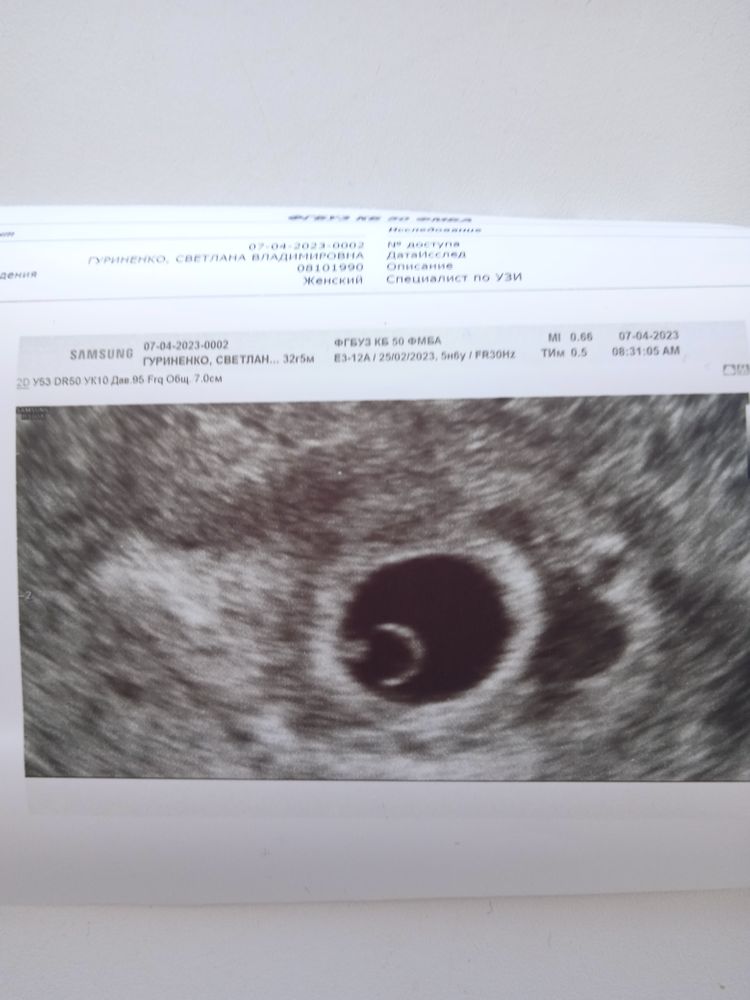

26 дпо или 5 недель 6 дней, расти мой 💍

Наш Василёк 🦦❣️Остаточная полость сохраняется, врач сказал норма, жить как обычно. СВД 12 мм, КТР 1.7 мм,желточный мешок 3.4 мм, пульсация первичной аорты +🙏Похвалила жёлтое тело, 24 мм. Желаю каждой женщине такое колечко с бриллиантом 🙏❣️💍